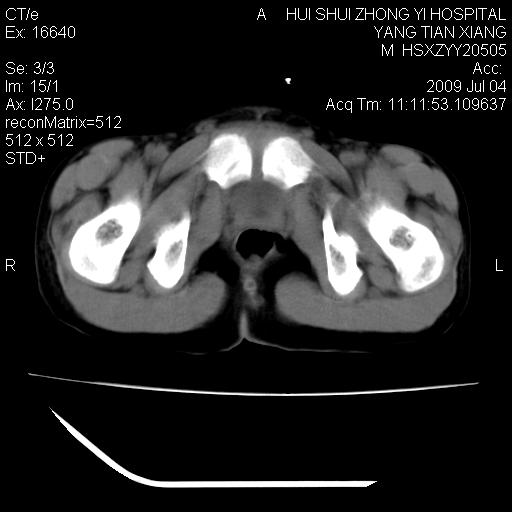

肝右叶胆管内见条状高密度影,脾脏增大,双肾上腺无异常;右肾正常结构消失,其实质内见类圆形低密度灶,ct值范围0-6hu,界清,右输尿管全程伴行多发低密度灶,界清,膀胱壁增厚,腹盆腔未见确切肿大淋巴结。

考虑:1、肝内多发胆管结石并肝内胆管扩张。2、右肾、输尿管多发脂肪瘤,多发平滑肌瘤?建议ct增强检查。4、膀胱壁增厚。

先天发育异常——巨输尿管(原发性梗阻性)可能性大!

1)考虑右侧巨输尿管畸形。2)肝内胆管多发性结石。3)脾大。

2、右侧巨输尿管并右肾积水可能性大。

右侧巨输尿管并神谕积水,左肾代偿性肥大,脾大,肝内胆管多发结石并胆管扩张。